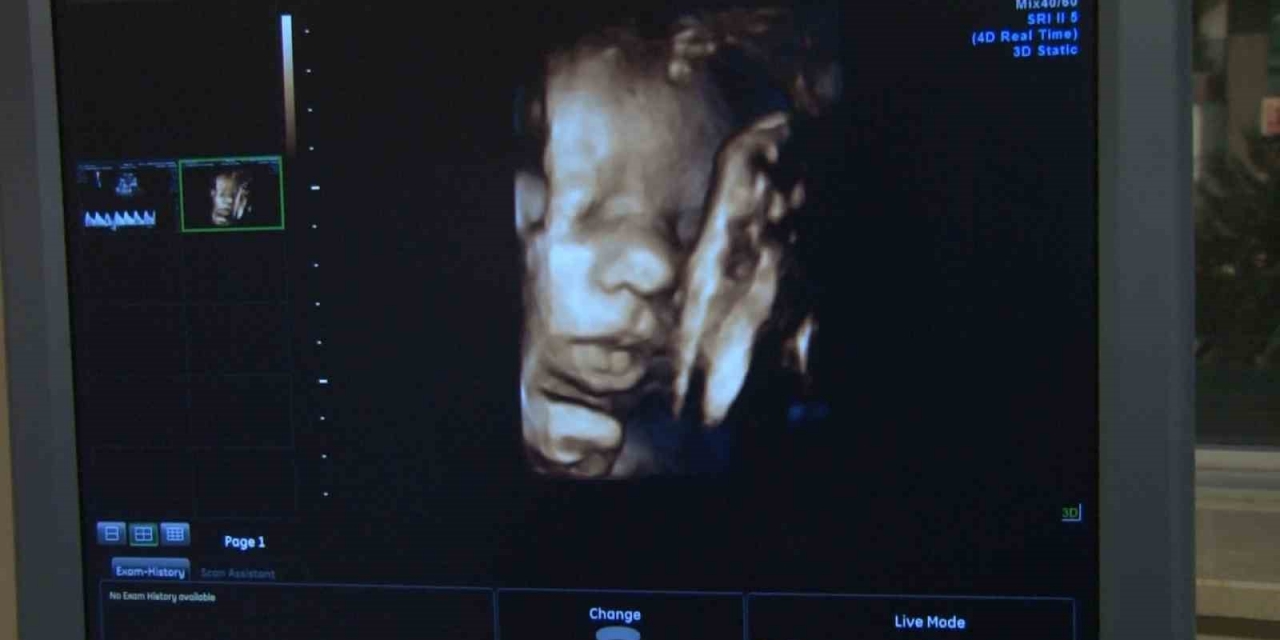

HIV virüsünün kadınlarda olan etkisini ve dünyaya getirdikleri bebeklerin doğum esnasında ya da emzirme süresince bulaştığını ifade eden Kadın Hastalıkları ve Doğum Uzamanı Op. Dr. Sibel Gökmen ise HIV pozitifli annenin gebelik sürecinde tedavisini düzenli bir şekilde alırsa HIV'li bir bebek dünyaya gelme ihtimalinin oldukça azaldığını söyledi. Op. Dr. Sibel Gökmen, "HIV'in anneden bebeğe bulaş yolu gebelik esnasında özellikle üçüncü trimester döneminde, doğum esnasında ya da emzirme süresince olabilir. HIV pozitifli anne gebelik sürecinde tedavisini düzenli bir şekilde alırsa HIV'li bir bebek dünyaya gelme ihtimali oldukça azalmaktadır. HIV'li bir annenin doğum sonrası bebeği emzirmesi önerilmemektedir. Ayrıca gebelik esnasında yapılan tanı ve tarama testleriyle annenin tanısını erken koyulması ve tedaviye başlanması sağlanabildiği için HIV'li bebek doğumları oldukça azalmış durumdadır. HIV'li bir bebeğin hayatını kaybetmesi gibi bir durum yok. HIV aslında Dünya Sağlık Örgütü tarafından kronik bir hastalık olarak değerlendirilmekte ve ömür boyu kontrol altına altında tutulabilmektedir" dedi.